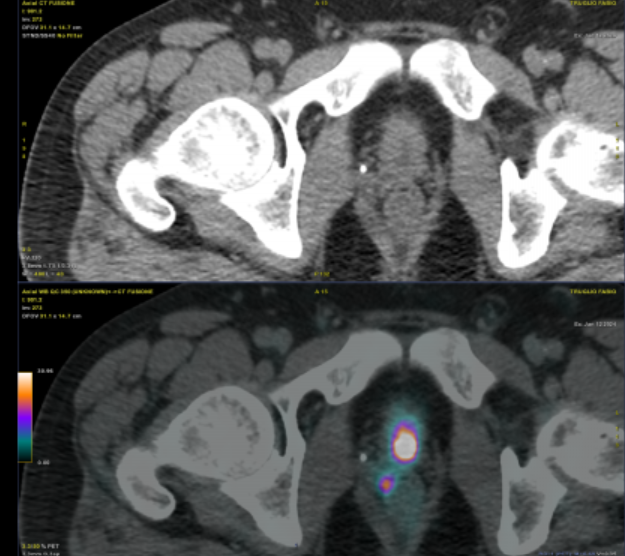

Long-term disease-free survival and health-related quality of life results of HDR brachytherapy as monotherapy pubmed.ncbi.nlm.nih.gov/39547869/

Long term outcomes for prospective trial of HDR monotherapy - very reassuring outcomes, despite most patients not being MR-staged at the time